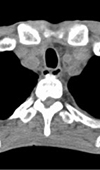

Infantile Acute Subdural Hematoma with Retinal Hemorrhage Caused by Minor Occipital Impact Witnessed by an ICU Nurse: A Case Report

An acute subdural hematoma (ASDH) in infants without external signs of trauma is differently recognized as shaken baby syndrome (SBS) or abusive head ... Read more

10.36959/595/406